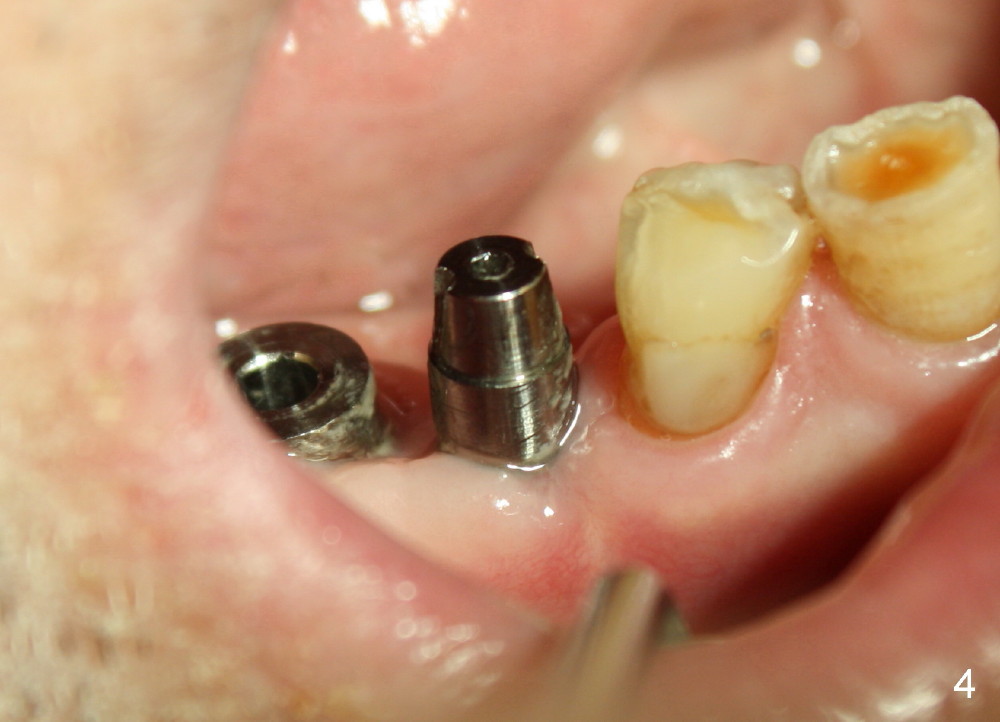

One month after implant placement at the sites of #29,30, the former is found loose (Fig.1,2). It is placed higher than #30. Three weeks later, PA is retaken to confirm that there is space apical to the implant at #29 (Fig.3 double arrows) and that there is distance from the mental loop (yellow dashed line). After infiltration anesthesia, the implant is torqued down initially (compare Fig.4,5) and more (Fig.6,7). To prevent re-loosening, the two implants are splinted (Fig.8).